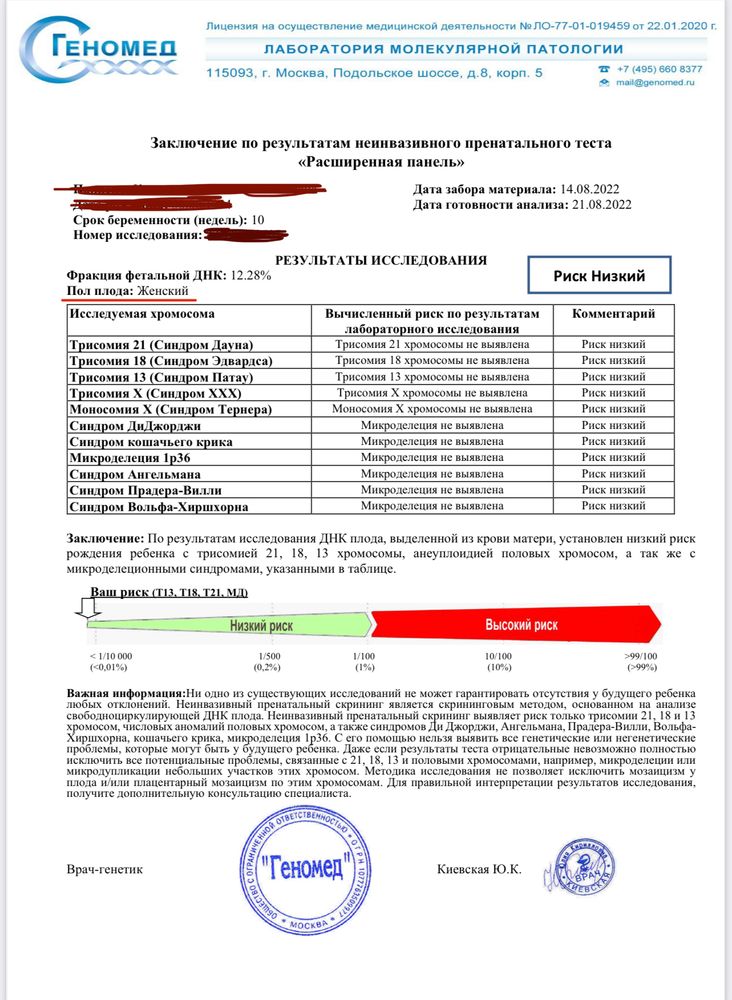

Всем привет)! У меня срок 11,4 и вчера пришел результат на НИПТ. Сдавала В 10,3 недель.

Что по срокам? Сдавала я расширенную панель в России. 14.08 я сдала кровь, 16.08 она поступила в лабораторию 21.08 в вс вечером пришел результат.

По результатам все хорошо! Малыш здоров, со спокойной душой пойду 29.08 на скрининг. Инициатива сдать такой тест полностью с мужем наша. Я вообще считаю что этот тест как в Америке должен быть у нас полностью бесплатным, а ещё лучше обязательным. Потому что статистика показывает, что 20% результатов скрининга ложно-отрицательные. Даже тот лучший врач города, которого я выбрала для скрининга допускал ошибки.

по НИПТ в итоге у нас девочка)